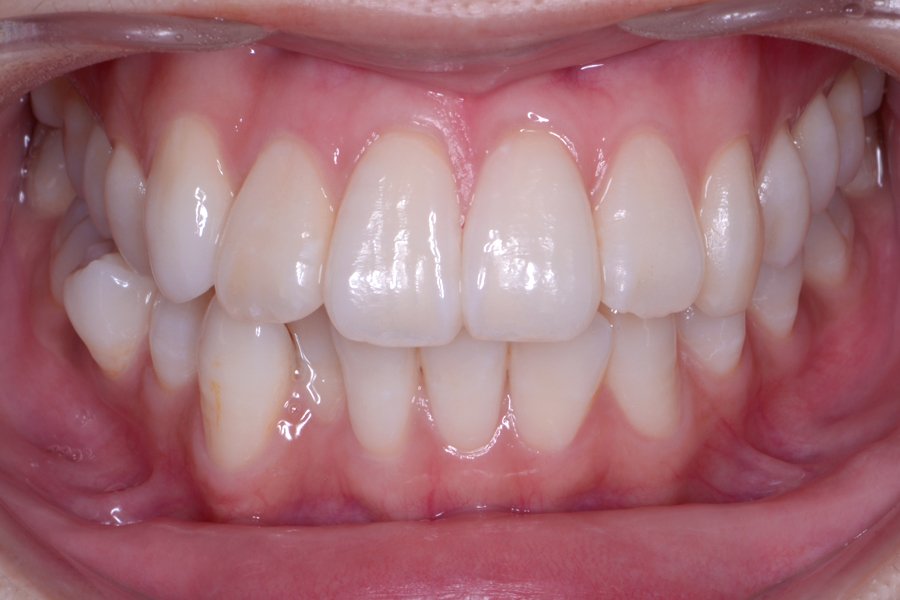

• 治療前

治療後

主訴 噛み合わせと前歯のすきっ歯を治したい

治療内容 上顎ラビアル矯正(表側矯正) リスク

リスク 後戻り